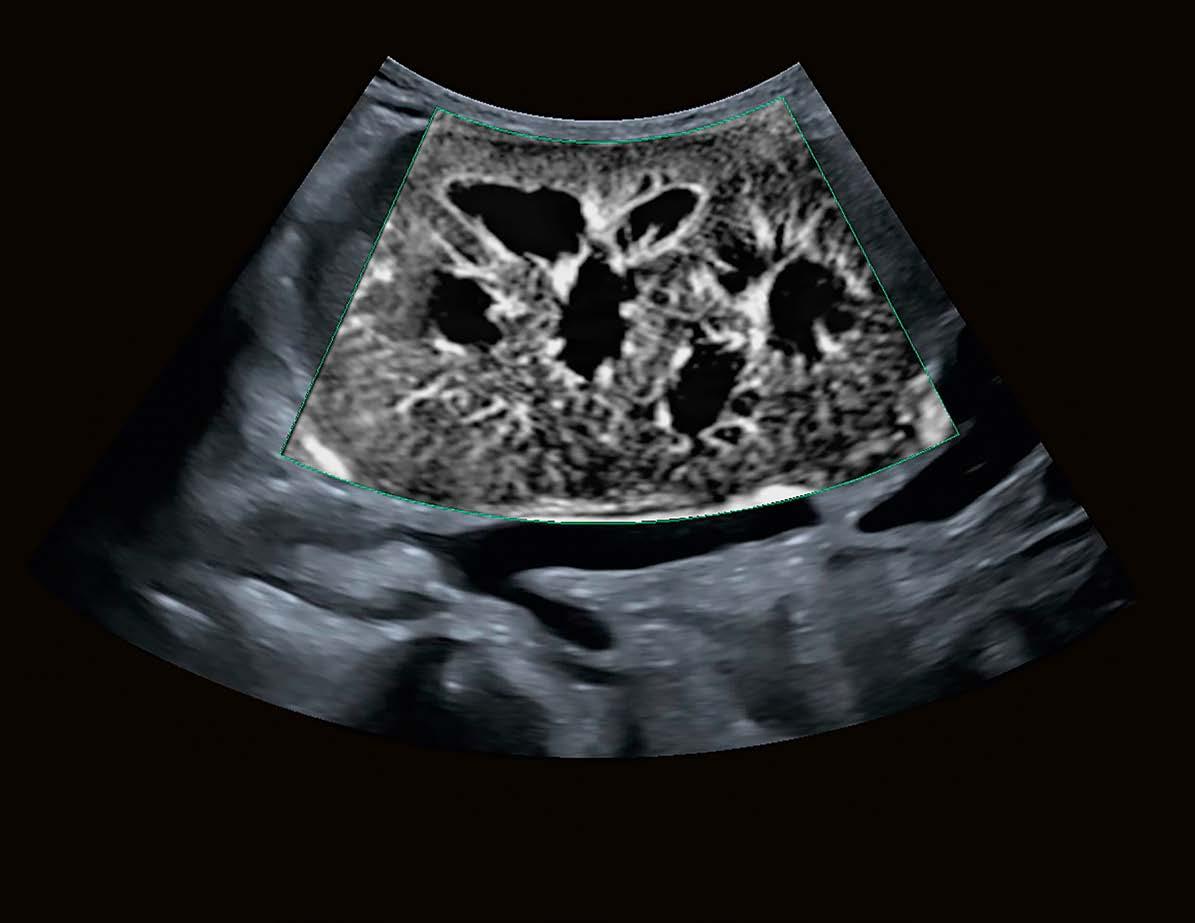

Die brandneue Aplio Prism Edition

Vor 20 Jahren präsentierte Canon Medical das erste AplioUltraschallsystem. Seit damals steht die Aplio-Serie für höchste Produkt- und Bildqualität in vielfältigen Anwendungsbereichen. Als Weiterentwicklung der erfolgreichen Aplio i-Serie ergänzt die brandneue Aplio i-Serie Prism Edition das UltraschallPortfolio. Hier setzt Canon Medical erstmals auch in seinen Ultraschallsystemen auf künstliche Intelligenz (KI): „Durch die Verbindung von Deep-Learning- und Machine-Learning-Algorithmen werden viele Arbeitsabläufe vereinfacht und standardisierte Messungen automatisiert. Somit werden Ultraschalluntersuchungen effizienter und die Messergebnisse reproduzierbarer“, erklärt DI Stefan Berger, MBA, Vertriebsleiter von Canon Medical Österreich.

Der technologische Fortschritt der

Aplio i-Serie Prism Edition ist sofort zu erkennen: Die revolutionäre iBeam+Architektur verfügt über eine bis zu viermal schnellere Verarbeitungsleistung von der Pulserzeugung bis zur Bilddarstellung. So bleibt die hohe Bildrate auch bei der Ultra-Wide-ViewDarstellung (140° Bildwinkel) und bei der vollautomatisch fokussierten Bilddarstellung (Full Focus) unverändert. Die Detailgenauigkeit im Bild ist bei der Aplio i-Serie Prism Edition auf einem exzellenten Niveau und wird von vielen Experten als „outstanding“ bezeichnet. Mit der iBeam+-Technologie wird die Orts- und Kontrastauflösung im Bild nochmals präzisiert und die Eindringtiefe weiter verbessert. Eine manuelle Fokussierung ist dafür nicht notwendig.

Ein weiterer Vorteil der Prism Edition ist die optimierte Ultra-Wide-ViewFunktion, die dem Anwender einen größeren Bildausschnitt liefert: Während normalerweise die Auflagefläche und -form eines Schallkopfs das Schallfeld definiert, kann dank Ultra Wide View das Sichtfeld um bis zu 100 Prozent auf einen 140°-Sektorwinkel erweitert werden. Bei der Aplio i-Serie Prism Edition funktioniert diese Erweiterung des Sichtfeldes ohne Verlust der Bildqualität oder der Bildrate.

SMI Generation 4 macht Unsichtbares sichtbar

Im Jahr 2015 wurde das Superb-microvascular-Imaging-Verfahren (SMI) erstmals vorgestellt. Seitdem hat sich SMI in der Darstellung kleinster Gefäße mit niedrigen Flussgeschwindigkeiten bewährt. Mit der Aplio i-Serie Prism Edition wird nun SMI der 4. Generation vorgestellt. Es ist für die Organperfusion sowie für die Beurteilung von Läsionen und Tumoren ausgezeichnet geeignet. Das Ergebnis: das bisher Unsichtbare wird sichtbar, bis zu Gefäßen im Submillimeterbereich.